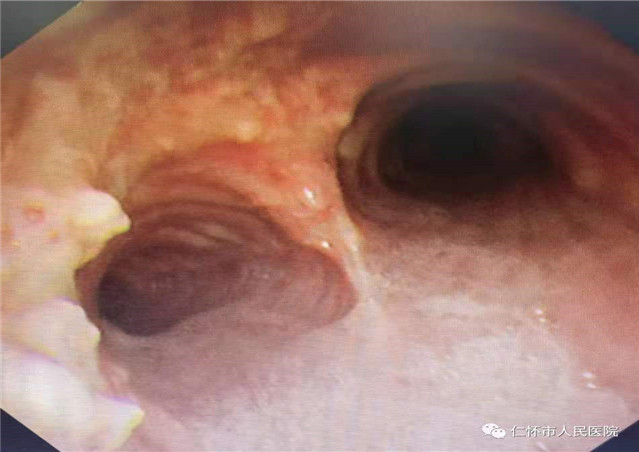

2021年5月24日,呼吸与危重症医学科刘婵副主任医师对患者行支气管镜检查,发现患者气管管腔不规则狭窄,前壁和侧壁黏膜下见多发大小不等、分布不均灰黄色的结节突向管腔,质硬,部分融合,刘婵在贵阳市第二人民医院(金阳医院)呼吸与危重症医学科帮扶专家何艳主任医师指导下成功取得病变组织10块送病理检查,后病理检查结果回示:气管骨化症。

骨化性气管支气管病( tracheobronchopathia osteochondro-plastica,TO)是指气管、支气管黏膜下有多发性骨质或软骨组织结节状增生并突向管腔的良性病变,能引起管壁变硬,管腔狭窄甚至阻塞。此病临床少见,其临床表现具有隐匿性,患者的症状轻重与病变范围、管腔阻塞程度有关,绝大多数患者早期没有症状,部分患者表现为咳嗽、咳痰、轻度咯血,喉部受累时常可出现声音嘶哑、咽部异物感、流涎、疼痛和吞咽困难。阻塞严重时可有呼吸困难,甚至可引起反复发作的肺炎或者肺不张。但由于这些症状缺乏特异性,往往易漏诊或误诊。

胸部X线以及普通的厚层CT对本病不敏感。薄层CT对气管、支气管壁结节内的钙化影相当敏感。气管、主支气管内多发的黏膜下小结节钙化影并突向管腔是TO较具特征性的CT表现。结节直径通常为1—10mm,位于气管和主支气管的前壁和侧壁,无蒂或有蒂,可散发或融合成片,质硬,触之易出血,黏膜可正常、充血、灰白、小血管显露或呈粉红色钟乳石样,管腔可变窄或不规则,后壁(气管膜部)极少受累,声门及声门以上组织、叶支气管及其远端支气管也很少受累。